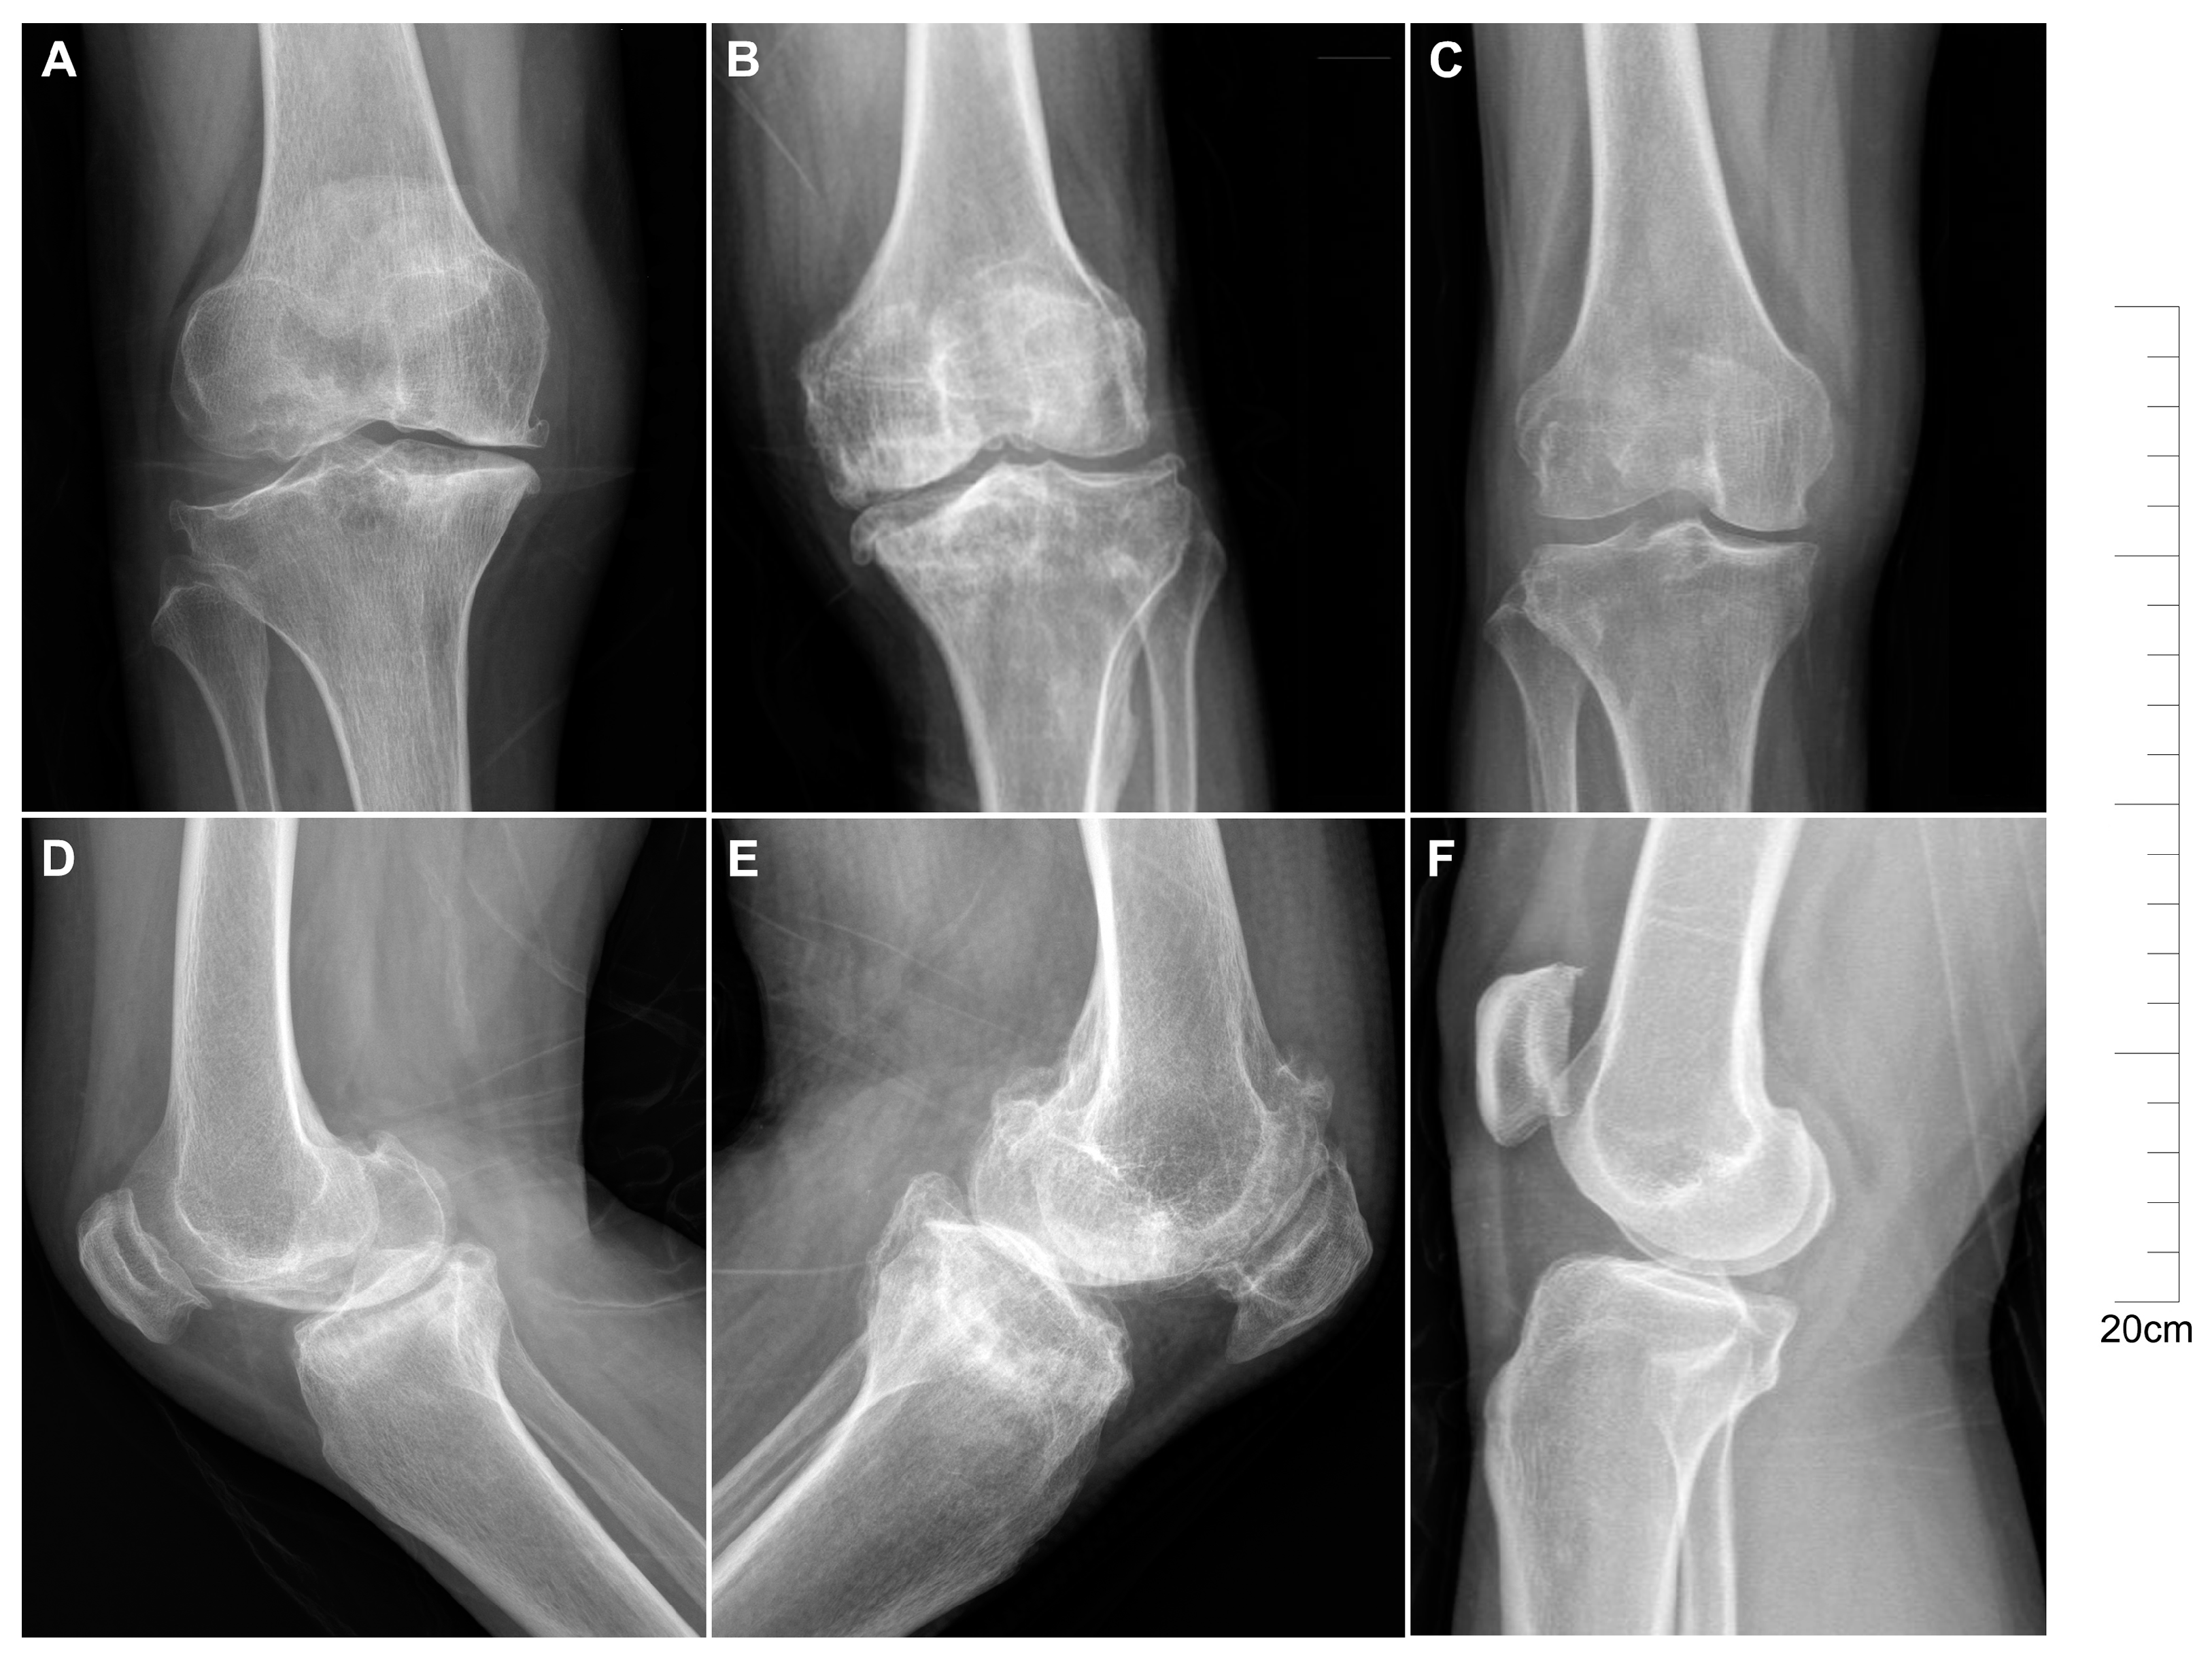

2.1. Descriptive Characteristics of Patients with KBD and OA

4.2. Patients and Samples